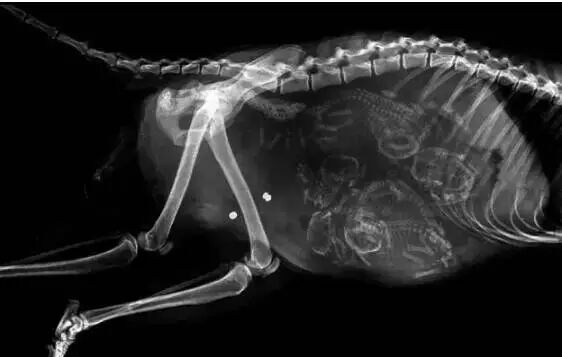

怀孕的猫

还是猫